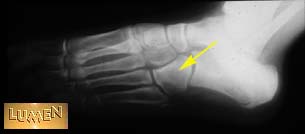

Question: Identify.

Cuboid.